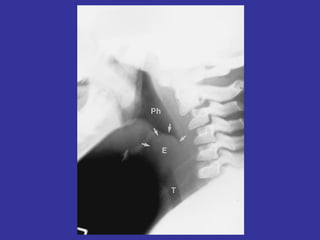

Bacterial: Retropharyngeal (tonsillar) abscess:  GABHS (S pyogenes) or St. aureus.  < 2 years. Fever, stridor, drooling, neck hyperextension w/ resistance to movement,  sore throat, hoarseness, trismus,  asymmetric tonsillar enlargement, Ant. Cervical nodes enlarged Severe Sx: dyspnea, SOB  Dx:  lateral neck films – increase in retropharyngeal space  Tx:  Emergency, hospitalization, surgical drainage, IV PCN or  Clindamycin Epiglottitis :  Hemophilus type B Children:  high fever, toxic, drooling, absence of cough Fungal: Candida (oral trush)-  on low imunosuppressed patients

Bacterial: Retropharyngeal (tonsillar)abscess: GABHS (S pyogenes) or St. aureus. < 2 years. Fever, stridor, drooling, neck hyperextension w/ resistance to movement, sore throat, hoarseness, trismus, asymmetric tonsillar enlargement, Ant. Cervical nodes enlarged Severe Sx: dyspnea, SOB Dx: lateral neck films – increase in retropharyngeal space Tx: Emergency, hospitalization, surgical drainage, IV PCN or Clindamycin Epiglottitis : Hemophilus type B Children: high fever, toxic, drooling, absence of cough Fungal: Candida (oral trush)- on low imunosuppressed patients